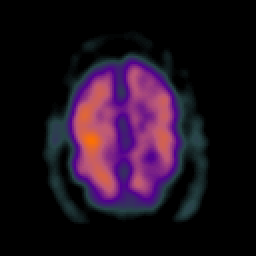

Subacute Stroke overlay -- Slice #19

[Home][Help][Clinical] Slice 19